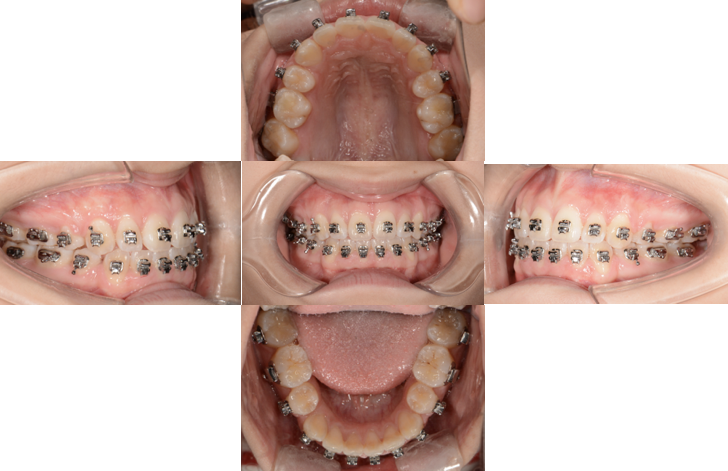

拔牙后,矫正器(如传统托槽、隐形牙套)会对牙齿施加持续、轻柔的牵引力,引导牙齿向拔牙间隙移动,这一过程依赖牙齿周围的牙槽骨改建:牵引力一侧牙槽骨吸收,另一侧新骨沉积,如同“电梯轨道”般使牙齿平稳移动,收缝速度因人而异,一般每月移动1-1.5mm,总时长取决于间隙大小与牙齿移动难度,通常需6-12个月,期间需定期复诊,医生通过调整矫正力确保牙齿沿正确方向移动,避免倾斜或扭转。

收缝过程中,口腔卫生维护至关重要,食物残易滞留在矫正器周围,需使用正畸专用牙刷、牙线间隙刷,预防龋齿和牙龈炎,饮食上避免过硬、黏性食物,防止矫正器脱落影响进度,部分患者可能出现牙齿酸胀、轻微疼痛,属正常现象,一般3-5天缓解。